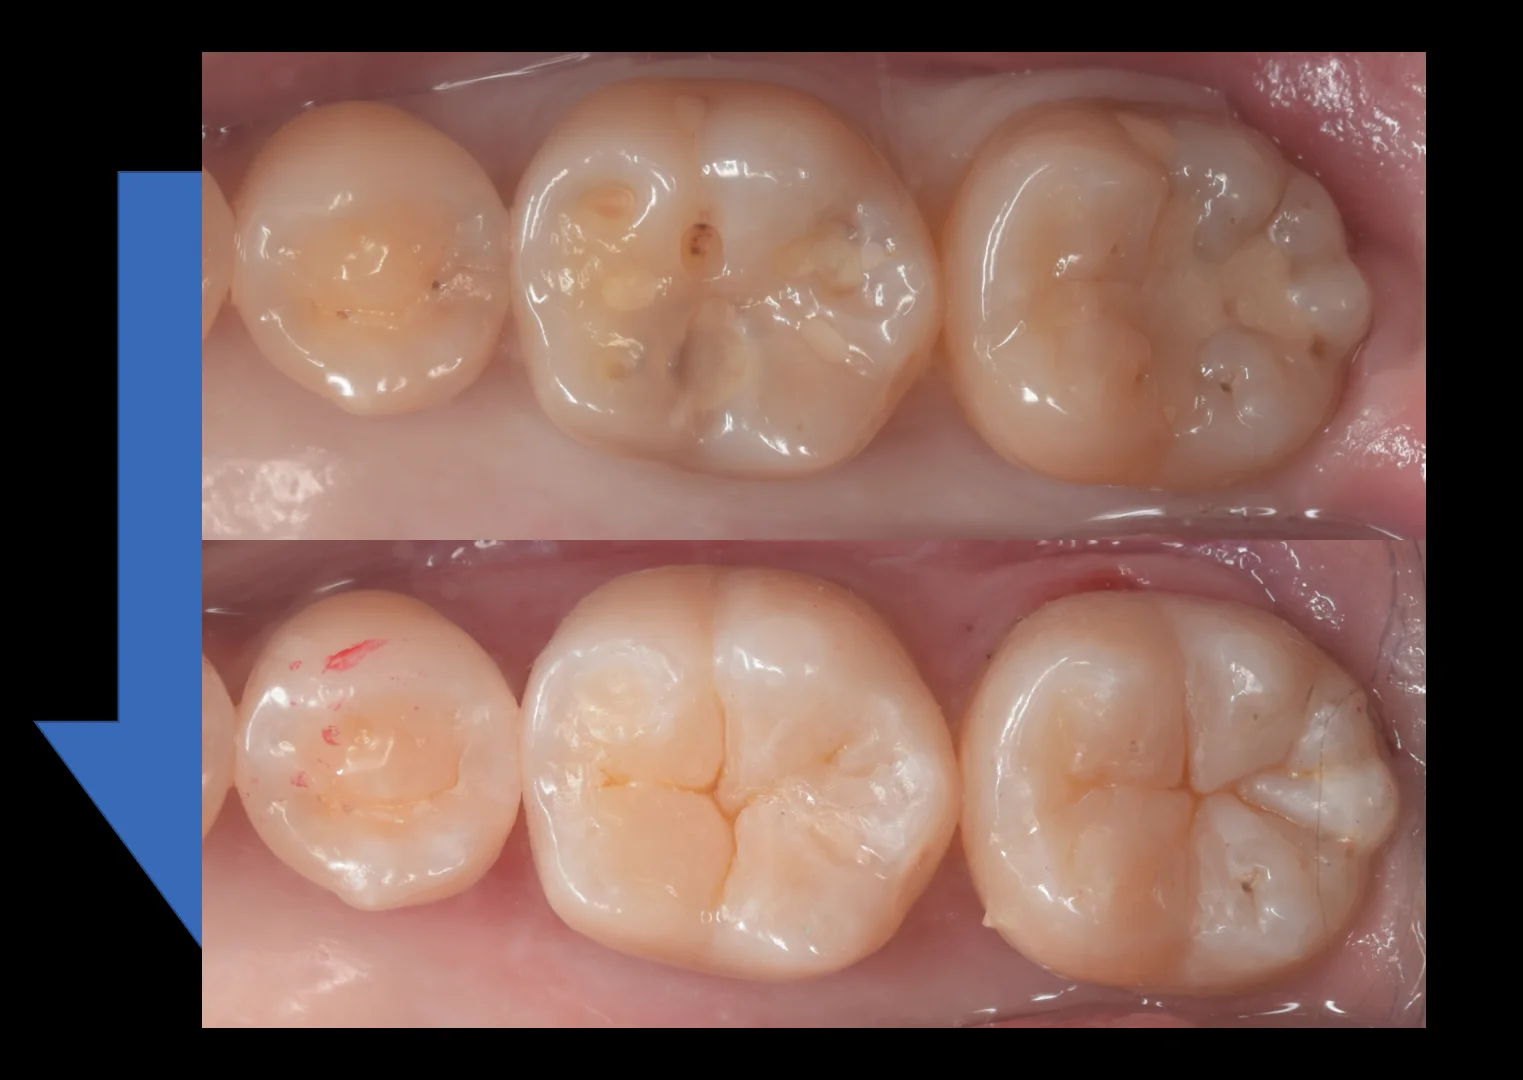

そして術前術後の写真がこちらです。

遠方より、長時間の治療お疲れ様でした!